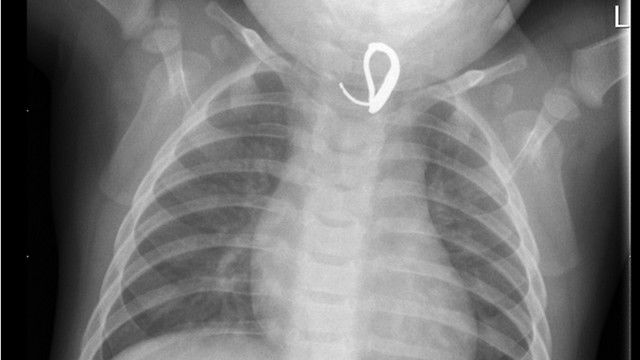

רופאי המרכז הרפואי שניידר, שלפו בסוף השבוע האחרון עגיל מתוך וושט של תינוק בן שמונה חודשים. הפעוט סבל במשך כשבוע וחצי משיעול טורדני ומחום גבוה ובתחילה סברו הרופאים כי הילד חווה מחלת חום סטנדרטית אך בצילום רנטגן התגלה עגיל בוושט.

ההורים סיפרו לרופאים כי הילד מסרב לאכול, חום גופו עלה ובנוסף הוא משתעל המון. כאמור בצילום רנטגן התגלה גוף זר בגופו של הילד, הרופאים נתקלו בקושי בשליפת העגיל שכן משך הזמן בו שהה העגיל בוושט הביא לכך שסוגר העגיל ננעץ בדופן הוושט ובנוסף הנוכחות של העגיל בגופו של הילד במשך כשבוע וחצי הובילה לגירוי ובצקת של רירית הוושט שהקשו אף הם על חילוץ העגיל, והדבר אילץ את הרופאים להוציא את החפץ הזר תוך תמרון עדין ובמטרה שלא לקרוע את רירית הוושט.